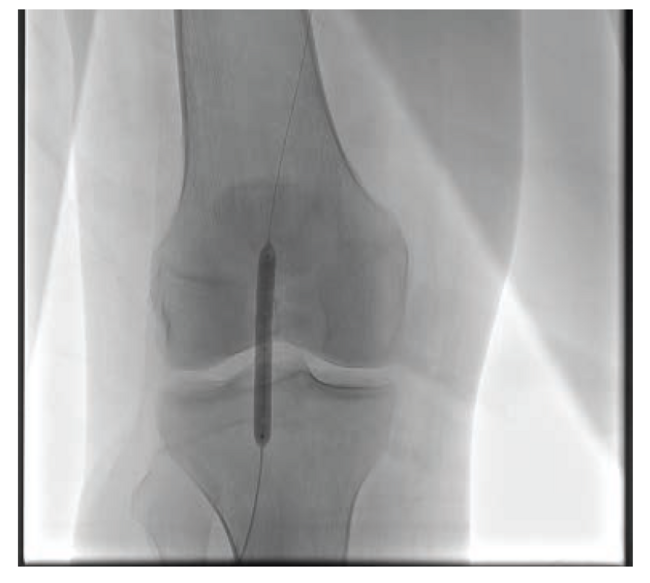

I recently treated a patient with nonhealing ulceration of his right great toe. He had a severely calcified lesion in his popliteal artery, as demonstrated in Figure 1. Due to the calcification, I performed intravascular lithotripsy with a 5.5 mm × 60 mm balloon (Figure 2). After balloon inflation, the lesion had a residual type C dissection (Figure 3). Therefore, I placed 3 tack devices across the area of dissection (Figure 4). Final angiography demonstrated no residual dissection or recoil (Figure 5).